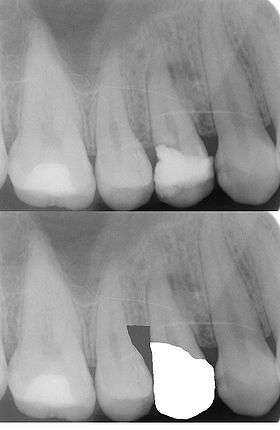

These two X-ray films depict the teeth of the upper right quadrant. In the upper film, there is a tooth, #5, with a large, defective DO composite restoration. The lower film depicts the ideal bone level after a crown lengthening procedure has been completed, as well as the margin of the prosthetic crown in relation to the reduced height of bone. Note: this is a dramatization of the procedure. The lower film is a digital manipulation of the upper film, and not an actual film of the teeth after a crown lengthening procedure and crown cementation have been performed.